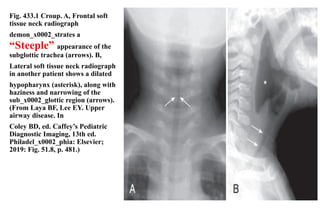

Fig. 433.1 Croup. A, Frontal soft

tissue neck radiograph

demon_x0002_strates a

“Steeple” appearance of the

subglottic trachea (arrows). B,

Lateral soft tissue neck radiograph

in another patient shows a dilated

hypopharynx (asterisk), along with

haziness and narrowing of the

sub_x0002_glottic region (arrows).

(From Laya BF, Lee EY. Upper

airway disease. In

Coley BD, ed. Caffey’s Pediatric

Diagnostic Imaging, 13th ed.

Philadel_x0002_phia: Elsevier;

2019: Fig. 51.8, p. 481.)